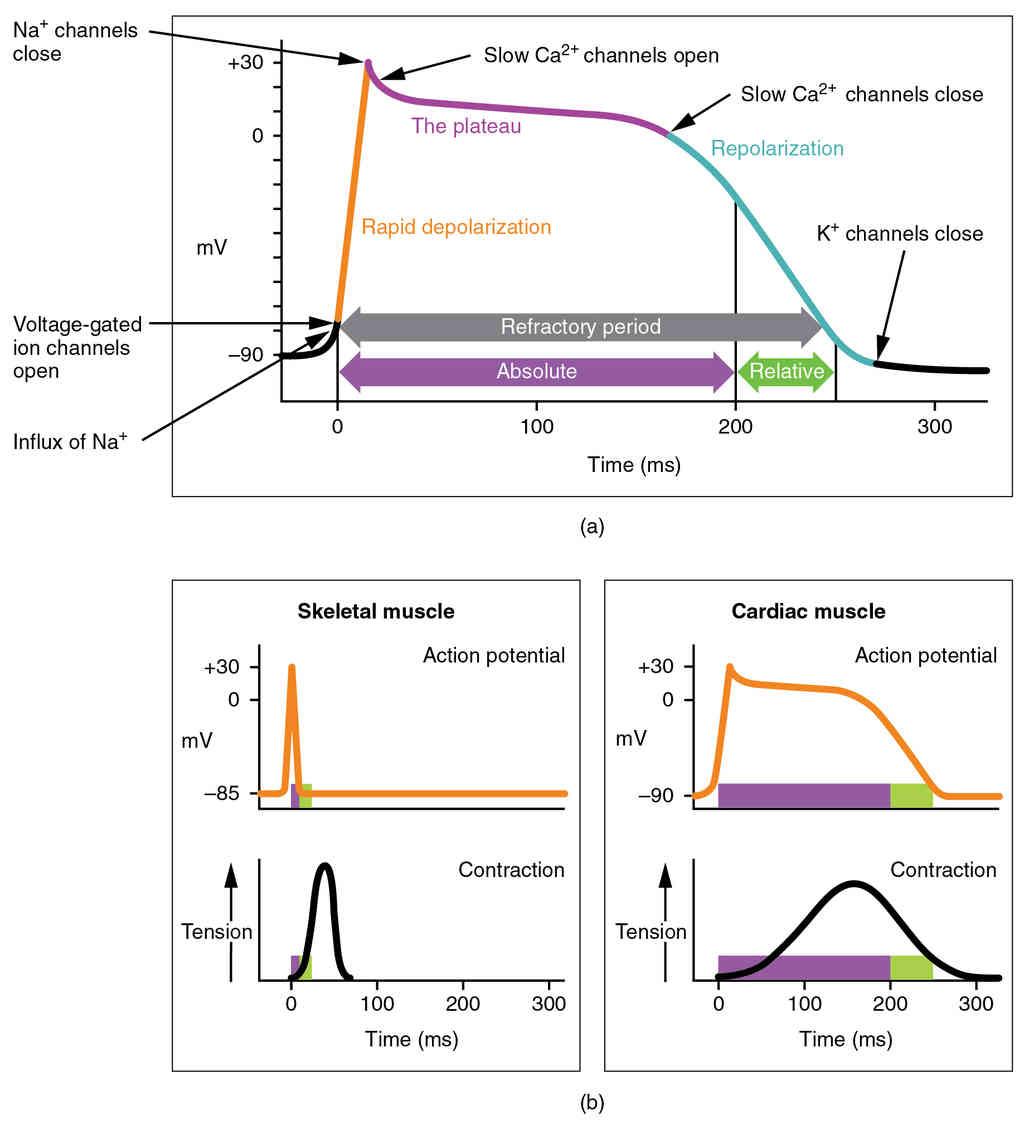

This page is under construction. For now, it is just a resource of the images found in the OpenStax Anatomy and Physiology Handbook. It wil slowly change into a revision tool. Each slide has a number. Use this to refer to the slide. When completed, it will have an unlabelled section, with labelled slides in parallel. On the unlabelled slides, write your answer and use the labelled slide to assess yourself. Keep track by also noting the number on each slide. Improvement at each attempt is important, more so than full marks on a first attempt.